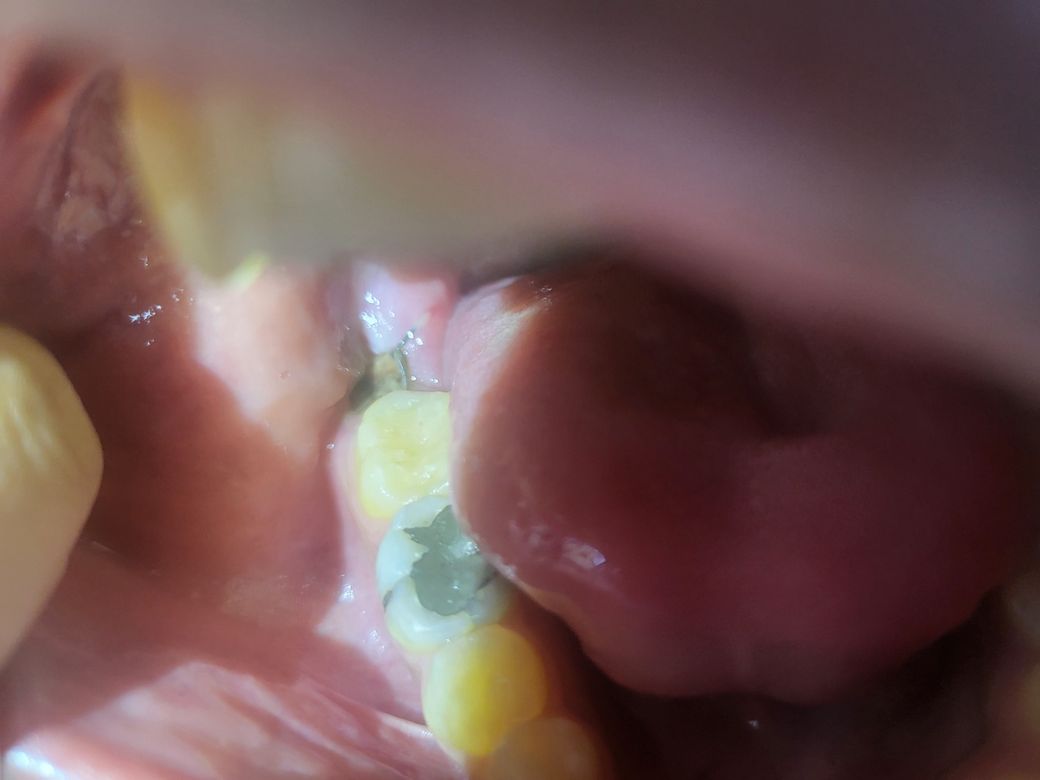

사랑니 발치후 발치 부위에 이상한게 생겼습니다

사랑니 발치 3일후에 사진과같이 발치부위에 이상한게 있는데

음식물이 낀거일까요? 통증은 없습니다 음식물이 낀거라면 바로 치과에 방문해야 할까요?

• 1번 째 사진